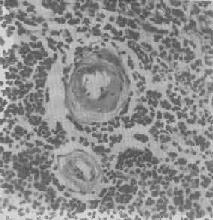

肾近曲小管上皮细胞玻璃样小滴变

图1-21 肾近曲小管上皮细胞玻璃样小滴变

上皮细胞胞浆内出现大小不等的均质圆形小滴

3.细胞内玻璃样变:亦称为细胞内玻璃样小滴变性。这种情况常见于肾小球肾炎或其他疾病而伴有明显蛋白尿时。此时肾近曲小管上皮细胞胞浆内可出现许多大小不等的圆形红染小滴(图1-21),这是血浆蛋白经肾小球滤出而又被肾小管上皮细胞吞饮的结果,并在胞浆内融合成玻璃样小滴,以后可被溶酶体所消化。此外,在酒精中毒时,肝细胞核周胞浆内亦可出现不甚规则的红染玻璃样物质。电镜下,这种物质由密集的细丝构成,据认为可能是细胞骨架中含角蛋白成分改变的结果,并被称为Mallory小体。